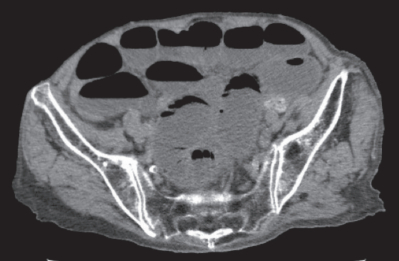

血液所見:赤血球 368 万、Hb 12.9 g/dL、Ht 36 %、白血球 15,600、血小板 21 万。血液生化学所見:総蛋白 6.5 g/dL、アルブミン 2.9 g/dL、総ビリルビン 0.9 mg/dL、AST 28 U/L、ALT 26 U/L、LD 287 U/L(基準 120~245)、CK 162 U/L(基準30~140)、尿素窒素 44 mg/dL、クレアチニン 1.8 mg/dL。CRP 4.7 mg/dL。来院時の骨盤部単純 CTを別に示す。